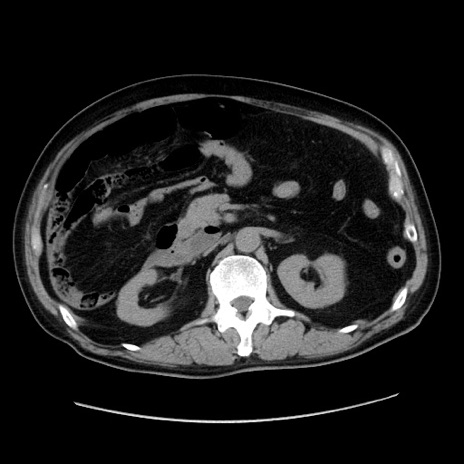

症例30(横断像)

【症例】80歳代男性

【主訴】臍周囲痛

【現病歴】約6時間前から臍下部痛が出現。次第に腹部膨隆・背部痛も生じてきたため来院。背部痛の場所は変化しない。

【身体所見】意識清明、BT 36.3℃、BP  131/87mmHg、P 87bpm、SpO2 100%(RA)、臍周囲自発痛・圧痛あり、反跳痛なし、自発痛部位に一致して板状硬あり、腹部膨隆、腸雑音減弱、CVA tenderness両側陰性。

【データ】WBC 19600、CRP 0.33